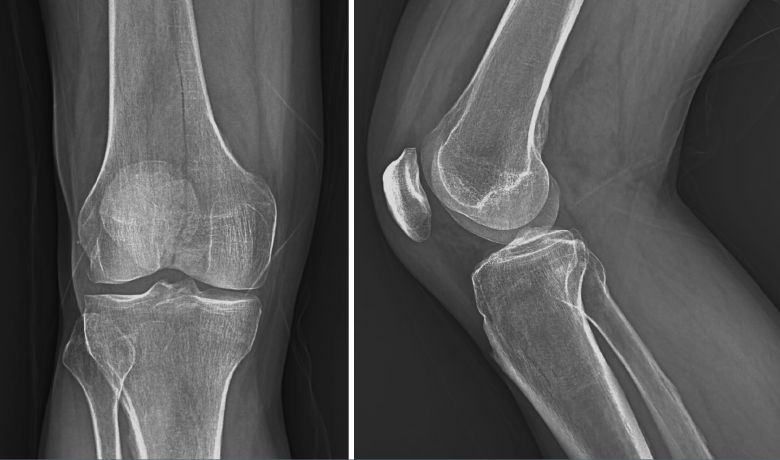

1.1.1. Fémur (Figura 1)

Figura 1. Radiografías anteroposterior y lateral de rodilla: fractura longitudinal del fémur extendida a la articulación.